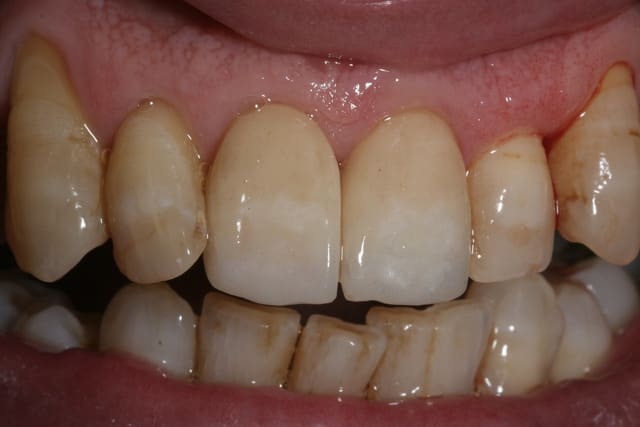

Je crois qu'effectivement la CAO peut être chiante, moi ça m'éclate. Il y a du boulot pour toutes les préférences et le travail de molinarius réunit le meilleur des deux mondes.

c'est du beau travail jumpingjack !

oui c'est du beau travail ..

Cependant je suis sure que ces types de cas ne se réalisent pas en deux temps trois mouvements!

il y du temps d'usinage , beaucoup de modelage pour parvenir à de tels cas et autant pour la finition .. donc on en revient toujours au même .. le temps que vous passez dessus vous ne le passez pas au fauteuil ...secu ou pas , votre rentabilité est ailleurs..

Sur le 1er cas de jump.... reconstitution au maxillaire , il y a plusieurs usinage(quelques heures) et un certain de temps finition à la pièce à main ... et sur d'autre plusieurs cuisson de maquillage sans doute ...

Que certains prats soient doués à jouer les prothésistes ;) c'est une chose mais je suis sure que c'est plus par plaisir de faire de la prothèse :) plutôt qu'un intérêt financier ... je me trompe jumpingjackflash ?